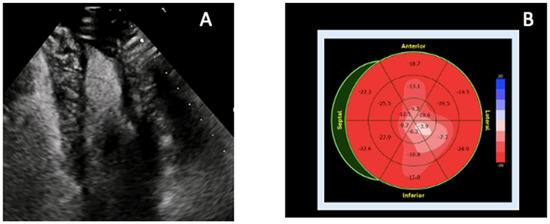

In addition to standardized lateral cephalometric radiographs, comprehensive assessment using dental cone-beam computed tomography (CBCT) and CT has become commonplace in the diagnosis and treatment of jaw deformities. Simulation based on cephalometr...